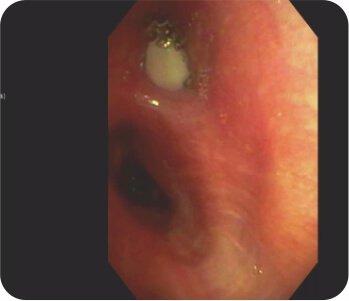

Bronchoscopy – Pus oozing from left upper lobe bronchus

Bronchoscopy – Mass/ Clot occluding the left upper lobe bronchus